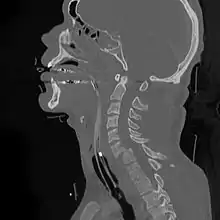

![]() | |

| A fracture of the base of the dens (a part of C2) as seen on CT. | |